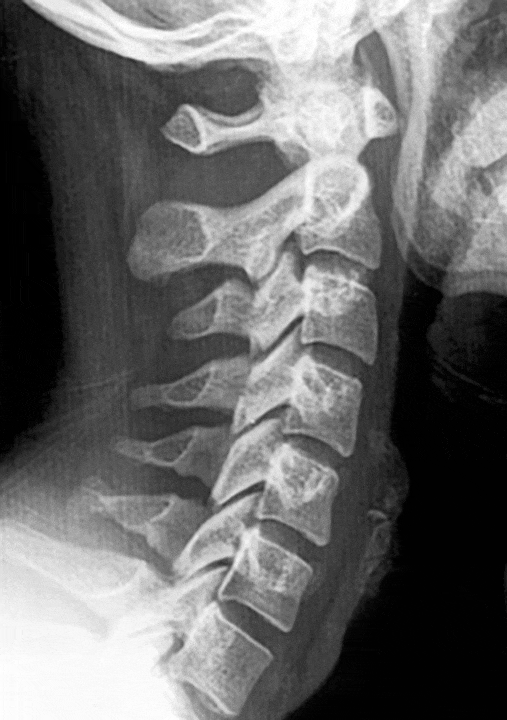

Straightening of the Cervical Lordosis

Straightening of the cervical lordosis, loss of cervical lordosis, and loss of physiological curvature are terms that describe the same condition, in which the cervical spine becomes abnormally straight, altering its natural curve.

After whiplash, the loss of physiological cervical lordosis is very common and often underestimated. Long-term consequences appear insidiously, with a negative impact on health.

If the straightening of the cervical lordosis persists without adequate correction, symptoms, whether mild or severe, tend to worsen, with the risk of developing irreversible degeneration of the cervical spine.

When consulting a doctor after an accident, attention is often focused on structural damage, such as fractures or other visible injuries. While these checks are essential for identifying serious issues, who addresses the functional problem? Is a physiotherapist consulted? Unfortunately, even then, the treatment is often symptomatic without effectively restoring the physiological cervical curvature.

To address this issue, we have developed a specific program to restore the natural curvature: straightening of the cervical lordosis.